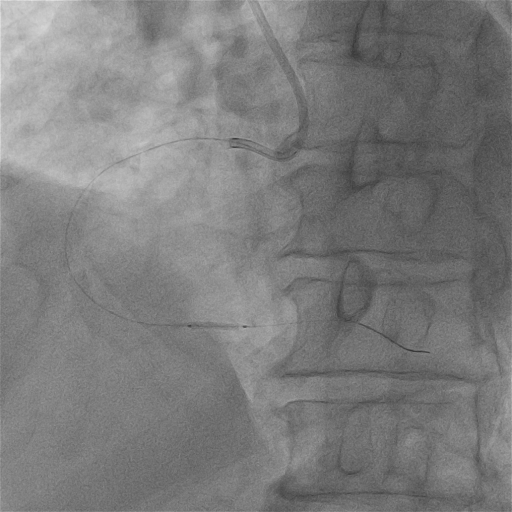

我院尝试SION blue工作导丝通过病变,阻力明显,Fielder XT-R导丝可到达远端

病变处狭窄及钙化严重,考虑普通微导管跟进困难,优先选择在纤细、迂曲的血管中通过性较好的“细径”微导管——HighTrack1.5Fr微导管,顺利通过病变后交换旋磨导丝至远端。